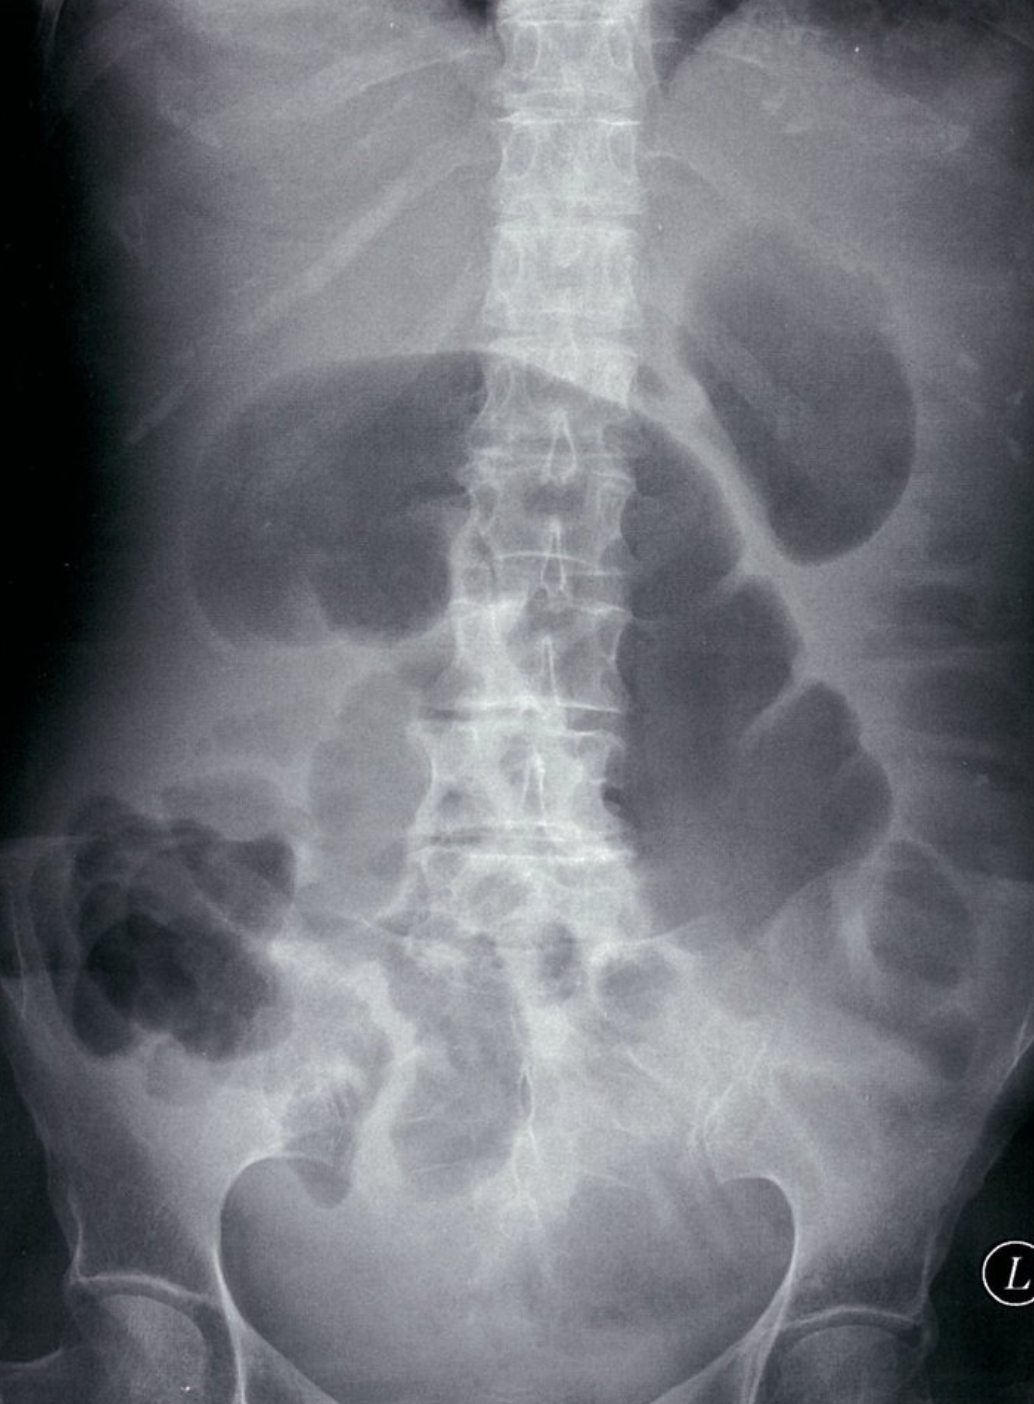

Small bowel dilatation

X-ray abdomen (AP view, supine) of a patient with distal small bowel obstruction

Multiple gas-filled, dilated (> 3 cm diameter) loops of bowel can be identified as small bowel loops by the presence of plicae circulares (green overlay).

This appearance on a supine abdominal radiograph may indicate ileus or distal obstruction. An erect or decubitus view is generally required to help distinguish ileus from obstruction.